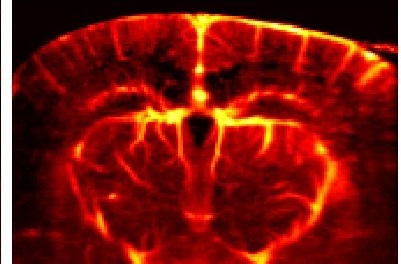

Recent ENG PhD Helps Develop Highly Sensitive Imaging Technique to Detect Myelin Damage

In a new study from Boston University Chobanian & Avedisian School of Medicine and BU’s College of Engineering, researchers used a special microscope called birefringence microscopy (BRM) paired with an automated deep learning algorithm to reliably count and map myelin damage across whole sections of the brain—something not feasible with other techniques. The ability to […]